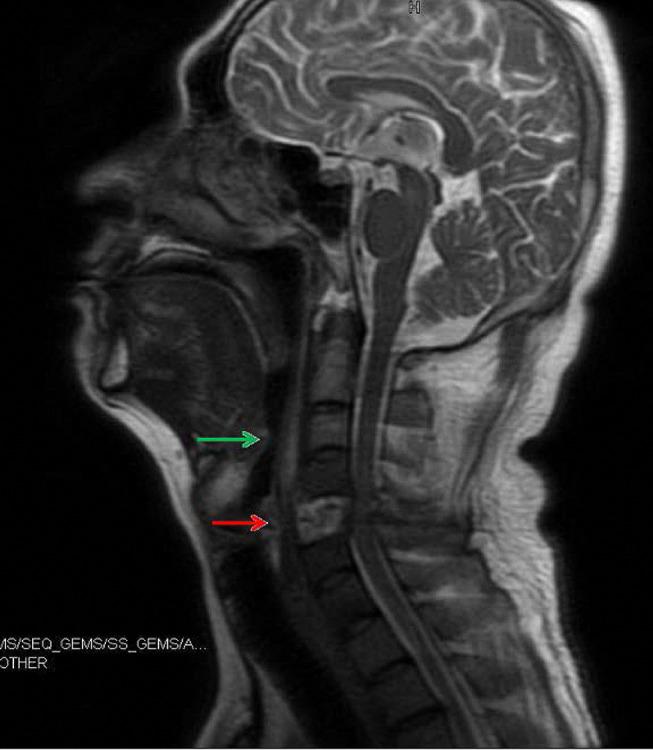

() is a causative pathogen of some rare diseases such as primary atrophic rhinitis and ozena. Here, we describe one case of a potentially lethal kind of infection in which multiple organs were implicated. A 40-year-old diabetic male patient presented to our hospital due to fever with right anterior chest mass and neck and shoulder pain for half a month. Based on all examination results, he was diagnosed with sepsis, bilateral pulmonary/right chest wall/liver abscesses and 5th cervical vertebra bone destruction with prevertebral abscesses, all related with infection. During the first time of admission, he was treated with antimicrobials without operations. Twelve days after his first discharge, fever and pain occurred again, the patient was treated with antimicrobials, operations (anterior debridement, spinal canal decompression, iliac bone graft fusion and internal fixation) and rehabilitation at second admission. The patient recovered well and was discharged from hospital. This case report demonstrates that can trigger a wide range invasive infections. Particularly, 5th cervical vertebra bone destruction was first reported as a clinical manifestation of infection in our patient.

()是一些罕见疾病如原发性萎缩性鼻炎和臭鼻症的致病病原体。在此,我们描述一例涉及多个器官的潜在致命性感染病例。一名40岁的糖尿病男性患者因发热伴右前胸肿块以及颈部和肩部疼痛半个月前来我院就诊。根据所有检查结果,他被诊断为脓毒症、双侧肺/右胸壁/肝脓肿以及第5颈椎骨质破坏伴椎前脓肿,所有这些均与()感染有关。首次入院时,他接受了抗菌药物治疗,未进行手术。首次出院12天后,发热和疼痛再次出现,患者在第二次入院时接受了抗菌药物治疗、手术(前路清创、椎管减压、髂骨植骨融合及内固定)和康复治疗。患者恢复良好并出院。该病例报告表明()可引发广泛的侵袭性感染。特别是,第5颈椎骨质破坏作为()感染的临床表现首次在我们的患者中被报道。